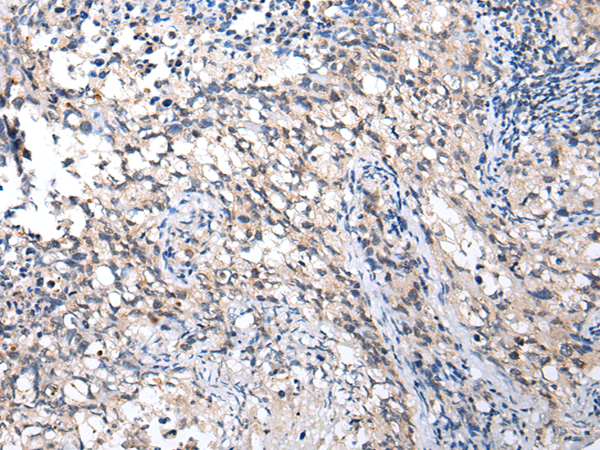

分类: 科研抗体货号: P02094别名: EMC5; TMEM32应用: WB,IHC反应种属: Human, Mouse, Rat